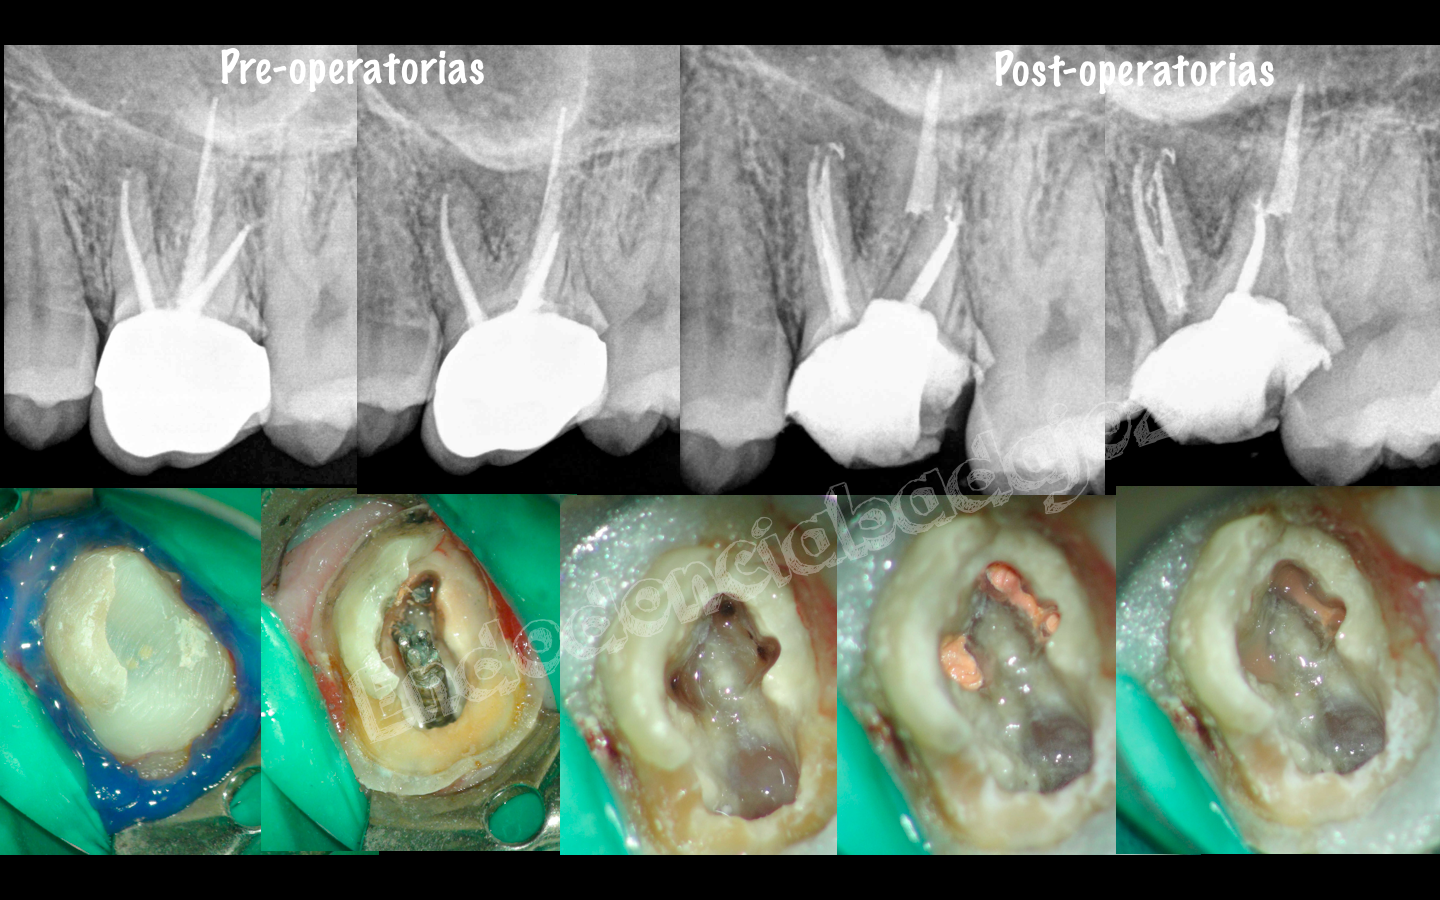

Después de una temporada sin postear ningún caso, hoy me levanté con ganas de publicar alguno, se trata de cinco casos, a mi juicio, interesantes, cuatro endodoncias de molares inferiores con anatomías complicadas y un retratamiento de un molar superior . Espero que os gusten.

• Hola Maru, cada retratamiento es diferente, según la condensación de la gutapercha, utilizo un sistema u otro. Pero generalmente, en este tipo de casos utilizo, las limas Protaper R y limas manuales ( C+ de Maillefer y Hedstrom del 15) hasta permeabilizar. Muchas gracias por tus palabras y espero haberte ayudado.

Aunque todos los casos son muy buenos, el tercero me parece muy bonito. Podría decirme a qué conducto se unía el MM? El preflaring cómo lo hace usted? Usa Gates o utiliza sistemas rotatorios NiTi?